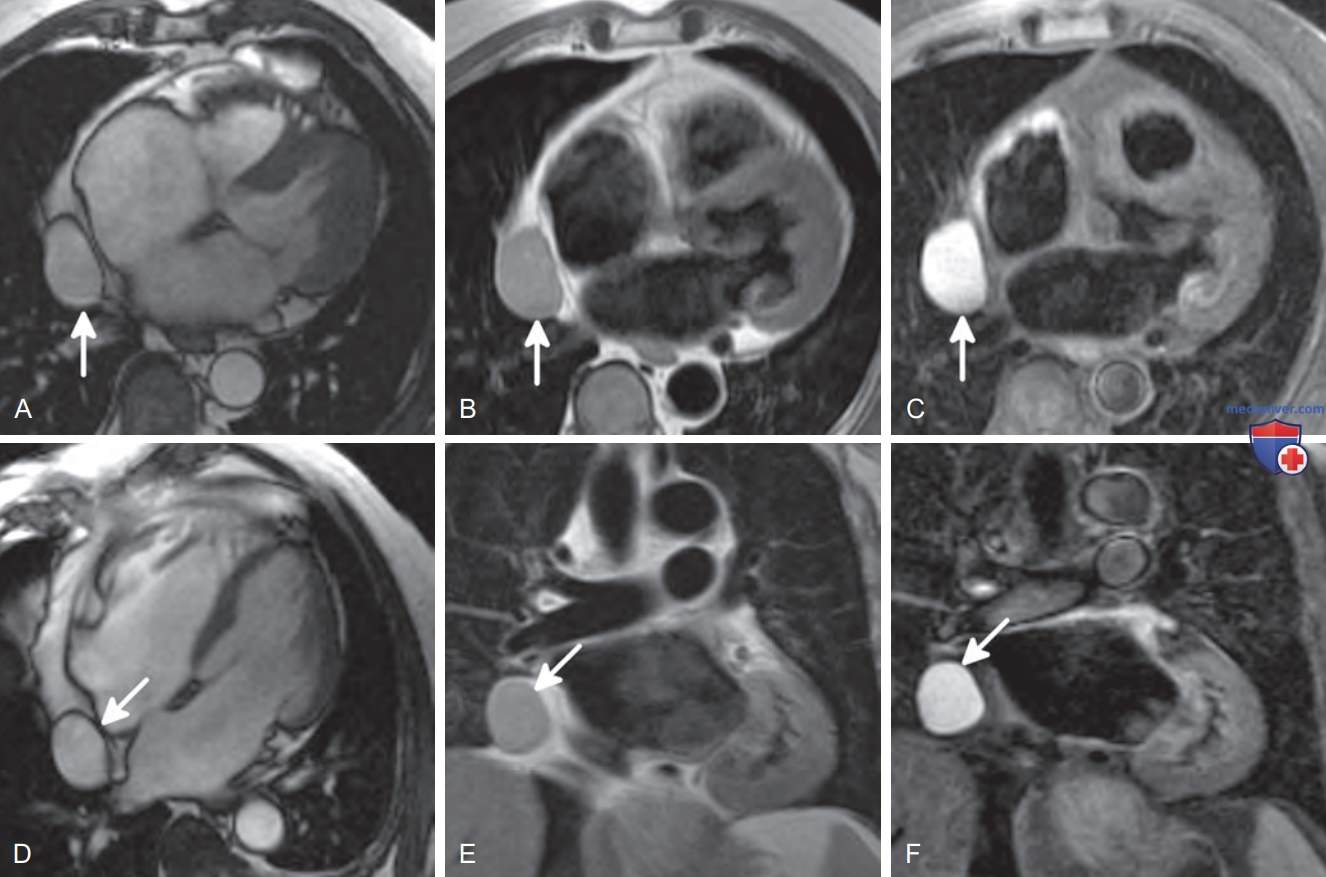

При МРТ эти кисты характеризуются низкой интенсивностью сигнала в Т1-взвешенных последовательностях и высокой интенсивностью в Т2-взвешенных последовательностях, и обычно не накапливают контраст (рис. ниже).

Перикардиальная киста на КТ и МРТ

Перикардиальные кисты с четкими границами и однородной интенсивностью сигнала (стрелки). (А) Аксиальное изображение, полученное в режиме быстрой визуализации с использованием сканирования в стабильном состоянии (FIESTA) в конце диастолы. Высокая интенсивность Т2-/Т1-сигнала, эквивалентная жидкости. (B) Аксиальное Т1-ВИ «черная кровь» быстрое спин-эхо (FSE): промежуточная интенсивность сигнала, связанная с белковым содержимым. (C) Аксиальное Т2-взвешенное изображение «черная кровь» FSE с жироподавлением (тройным): высокая интенсивность Т2/Т1-сигнала, эквивалентная сигналу жидкости. (D) 4К изображение в режиме FIESTA в конце диастолы: высокая интенсивность Т27Т1-сигнала, эквивалентная сигналу жидкости. (E) Фронтальное Т1-взвешенное изображение «черная кровь» FSE: промежуточная интенсивность сигнала, связанная с белковым содержимым. (F) Фронтальное Т2-ВИ «черная кровь» FSE с жироподавлением (тройным): высокая интенсивность Т2-/Т1-сигнала, эквивалентная сигналу жидкости

Перикардиальные кисты с белковым или геморрагическим содержимым могут характеризоваться промежуточной плотностью при КТ и высоким или промежуточным сигналом на Т1-ВИ.